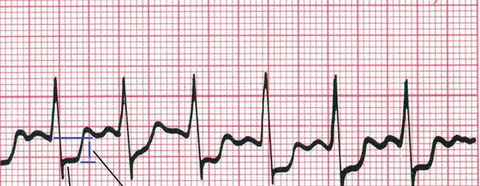

Introduce tu texto aquí... Flutter auricular